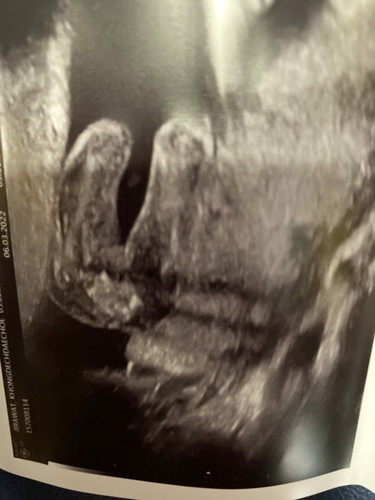

อัลตราซาวด์มา ญ หรือ ช ดูออกมั้ยค่ะ หมอยังไม่ฟันธง

วันนี้ไปอัลตราซาวด์มา ครบ 20 สัปดาห์ แต่เพศหมอยังไม่ฟันธง ค่ะ ดูยาก

ผญมั้ยคะไม่มีอะไรโด่ออกมา แม่บ้านนี้อยากให้เป้นกลีบจังแต่ซาวแต่ละทีจู๋โผล่ตลอดเลย🤣🤣

หน้าจะผู้หญิงค่ะเพราะถ้าผู้ชายจะเห็นจู๋ชัดเจนค่ะ

น่าจะหญิงนะคะ ถ้าชายจะเห็นจู๋ชัดเจนเลย